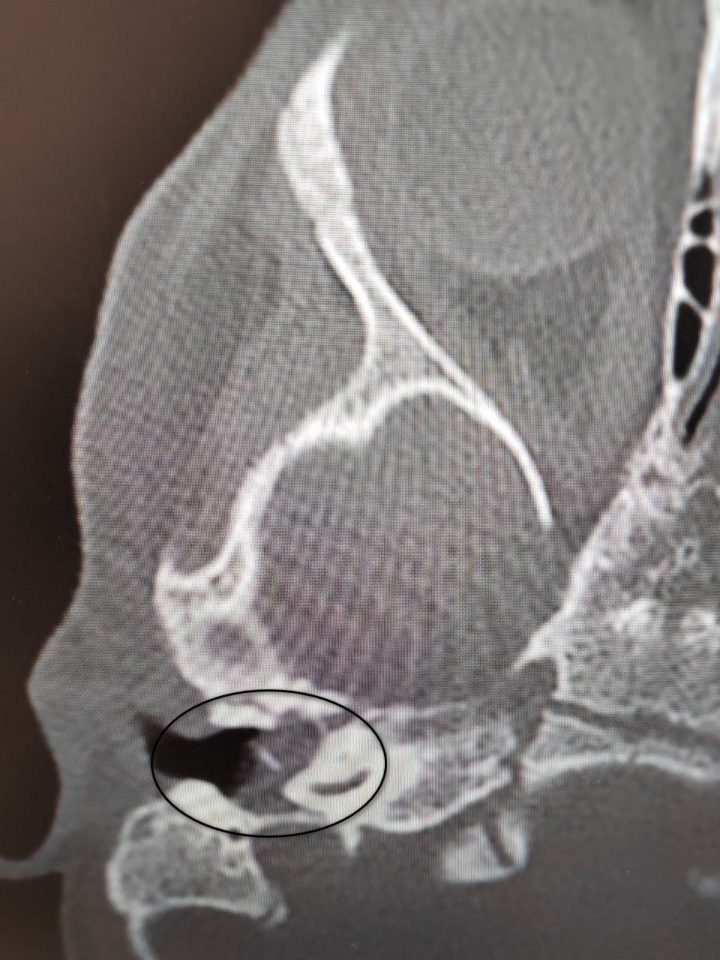

Крошка поступила в оториноларингологическое отделение с хроническим гнойным средним отитом и подозрением на врождённую холестеатому барабанной полости (кистозное патологическое образование в среднем ухе). Это заболевание обычно диагностируют позже: у детей пяти-восьми лет. Холестеатома опасна тем, что может привести к повторяющемуся гноетечению и разрушению структур среднего уха, которые отвечают за слух.

Обследование показало: диагноз малышки – врождённая холестеатома. Врачи решили делать операцию. Под операционным микроскопом хирург удалил холестеатому, провёл декомпрессию лицевого нерва и восстановил механизм звукопроведения.